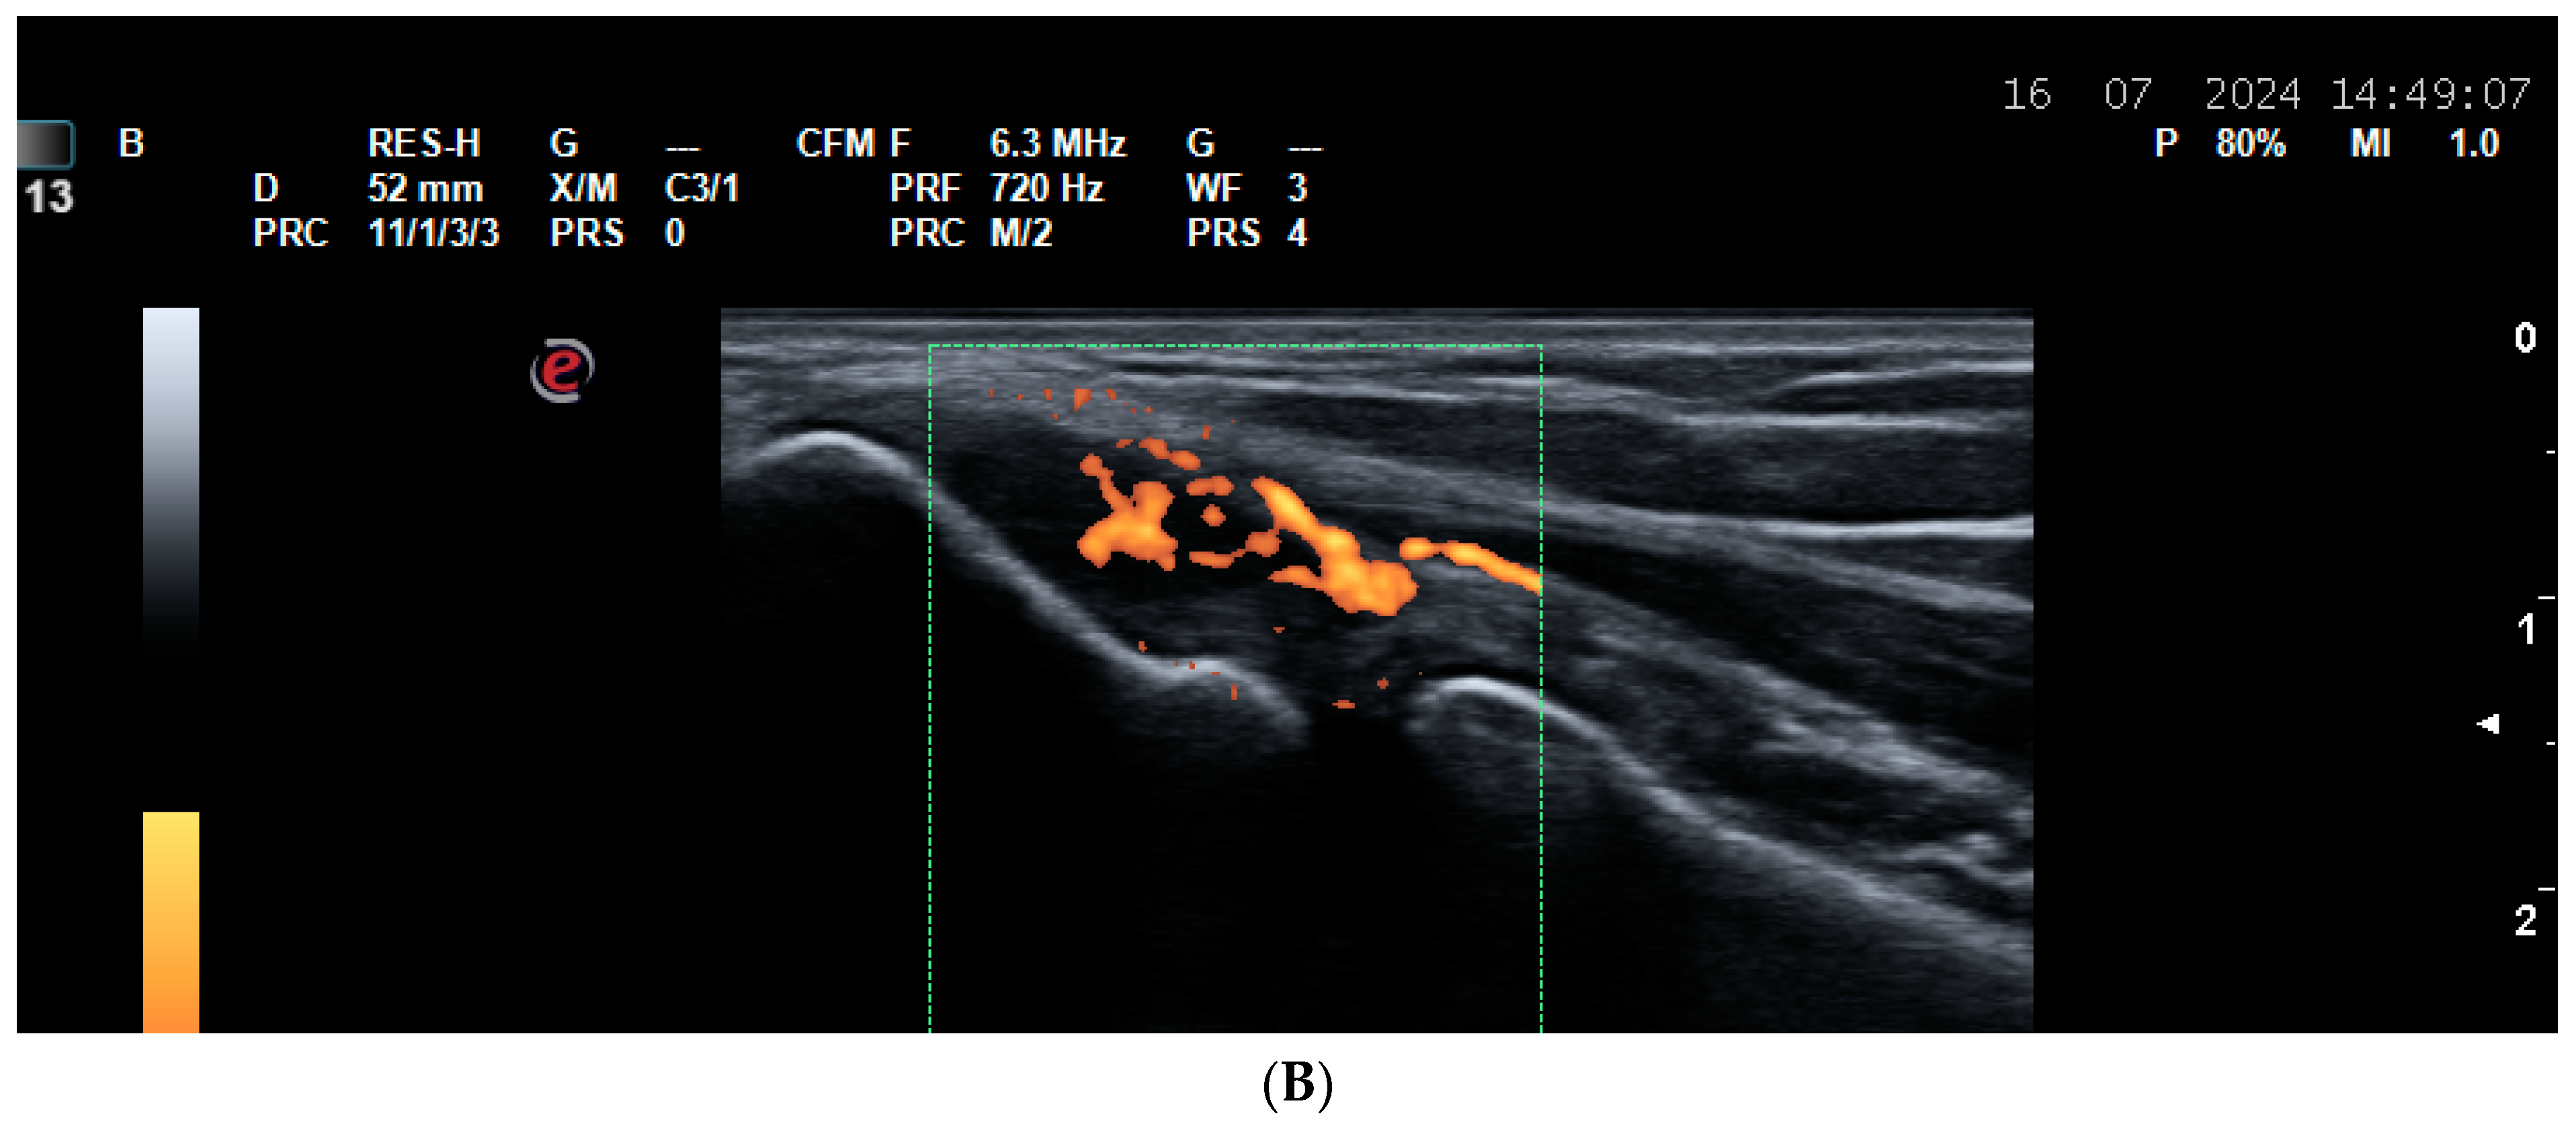

5.2. Vasculitides